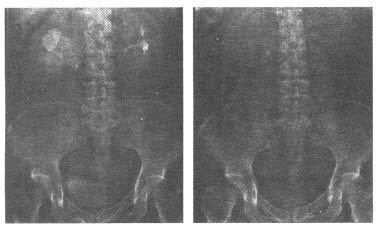

13、单项选择题

男,46岁,双髋部疼痛,实验室检查血钙升高,尿本周蛋白(+),结合图像,最可能的诊断是()

A.肺癌

B.肺结核